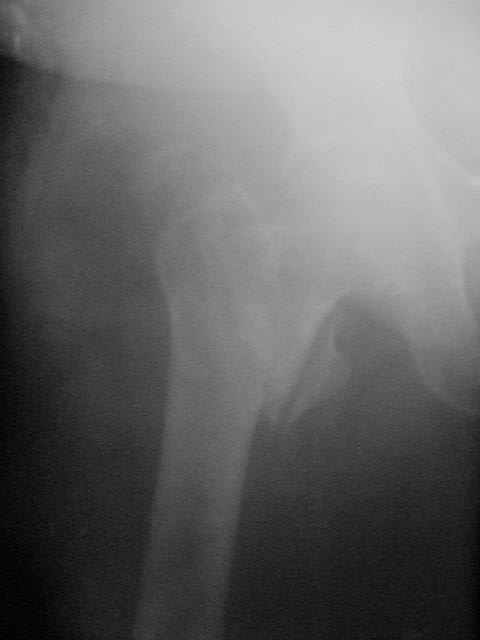

Здравствуйте коллеги ! Прооперировали женщину 72 лет с Диагнозом: Чрезвертельный перелом левого бедра.

Первый раз поставили PFN A (SYNTHES) см R-gr. У нас возникли споры в каких случаях и в каком возрасте проводить дистальное блокирование - в смысле: Статическое или Динамическое? при таких переломах. В какие сроки и на сколько давать нагрузку, движения именно у геронтологических больных? С Уважением Владимир Бахарев.